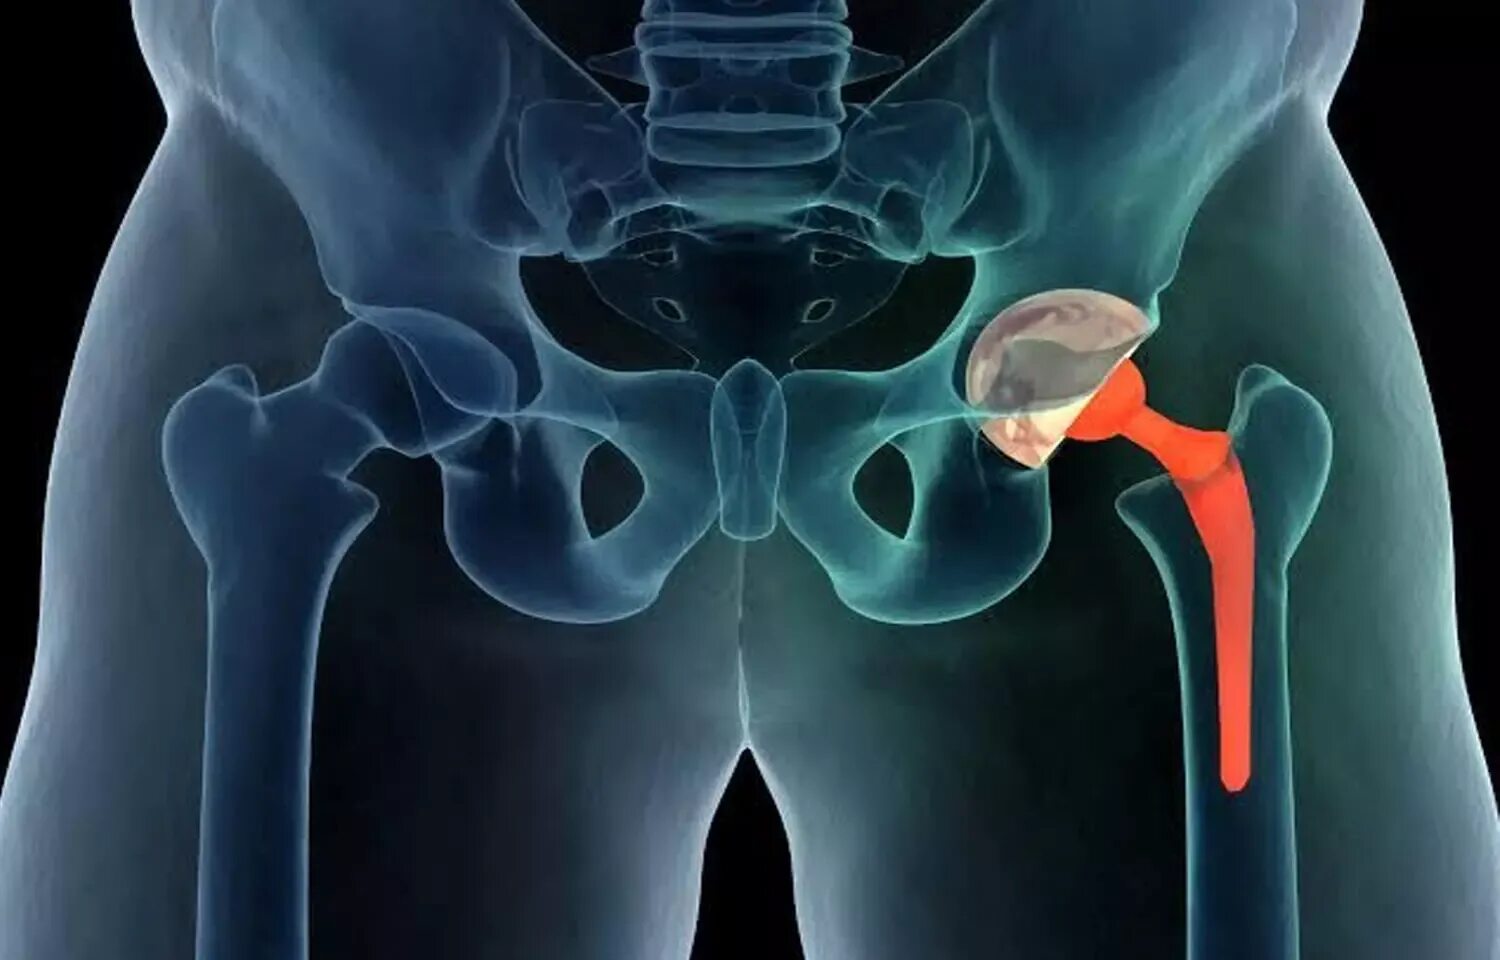

Hip 3. Упражнение хождение на ягодицах. Hip robot joint. Hip 3. Искусственный тазобедренный сустав.

Hip 3. Упражнение хождение на ягодицах. Hip robot joint. Hip 3. Искусственный тазобедренный сустав.

Тазобедренный сустав 3 д. Тазобедренная кость человека. Боль в тазобедренном суставе. Тазобедренный эндопротез райт. Hip 3.

Тазобедренный сустав 3 д. Тазобедренная кость человека. Боль в тазобедренном суставе. Тазобедренный эндопротез райт. Hip 3.

Эндопротезирование тазобедренного сустава операция. Hip 3. Операция эндопротез тазобедренный. Онкологический эндопротез тазобедренного сустава. Тазобедренный сустав 3d.

Эндопротезирование тазобедренного сустава операция. Hip 3. Операция эндопротез тазобедренный. Онкологический эндопротез тазобедренного сустава. Тазобедренный сустав 3d.

Протез тазобедренного сустава. Тазобедренный сустав болит. Артропластика тазобедренного сустава. Hip 3. Ходьба на ягодицах.

Протез тазобедренного сустава. Тазобедренный сустав болит. Артропластика тазобедренного сустава. Hip 3. Ходьба на ягодицах.

Упражнение ходьба на ягодицах. Замена тазобедренного сустава. Hip 3. Hip 3. Эндопротез тазобедренного сустава.

Упражнение ходьба на ягодицах. Замена тазобедренного сустава. Hip 3. Hip 3. Эндопротез тазобедренного сустава.

Тазобедренный сустав анатомия. Искусственный тазобедренный сустав. Гемиартропластика тазобедренного сустава. Hip 3. Эндопротезирование костей таза рентген.

Тазобедренный сустав анатомия. Искусственный тазобедренный сустав. Гемиартропластика тазобедренного сустава. Hip 3. Эндопротезирование костей таза рентген.

Эндопротезирование тазобедренного сустава. Тазобедренный протез. Hip 3. Тазобедренный сустав иконка. Medicad 2d hospital expert.

Эндопротезирование тазобедренного сустава. Тазобедренный протез. Hip 3. Тазобедренный сустав иконка. Medicad 2d hospital expert.

Красивые ноги. Тренажер technogym glute. Эндопротез тазобедренного сустава джонсон и джонсон. Тазобедренный эндопротез зиммер. Hip joint.

Красивые ноги. Тренажер technogym glute. Эндопротез тазобедренного сустава джонсон и джонсон. Тазобедренный эндопротез зиммер. Hip joint.

Анатомия вертлужной впадины тазобедренного сустава. Эндопротезирование тазобедренного сустава. Трохантерита тазобедренного сустава. 3hip. Coxa vara тазобедренного сустава.

Анатомия вертлужной впадины тазобедренного сустава. Эндопротезирование тазобедренного сустава. Трохантерита тазобедренного сустава. 3hip. Coxa vara тазобедренного сустава.

Тазобедренный сустав. 3д модель сустава. Hip 3. Hip abduction тренажер. Hip replacement.

Тазобедренный сустав. 3д модель сустава. Hip 3. Hip abduction тренажер. Hip replacement.

Эндопротез тазобедренного сустава. Medicad. Coxa vara тазобедренного сустава. Скелет человека тазобедренный сустав. 3д модель сустава.

Эндопротез тазобедренного сустава. Medicad. Coxa vara тазобедренного сустава. Скелет человека тазобедренный сустав. 3д модель сустава.